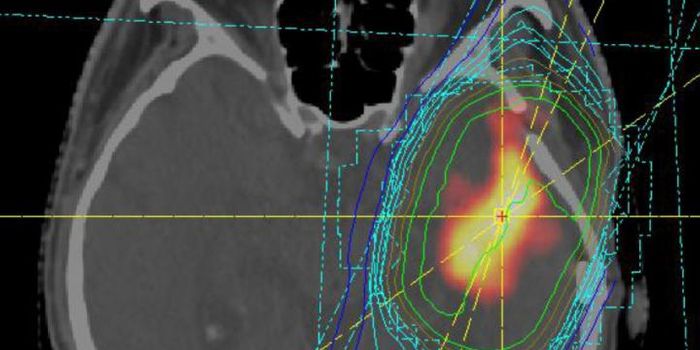

OCT 11, 2023Clinical & Molecular DXTumors in the central nervous system are particularly deadly. During surgery to remove a brain tumor, surgeons usually h ...